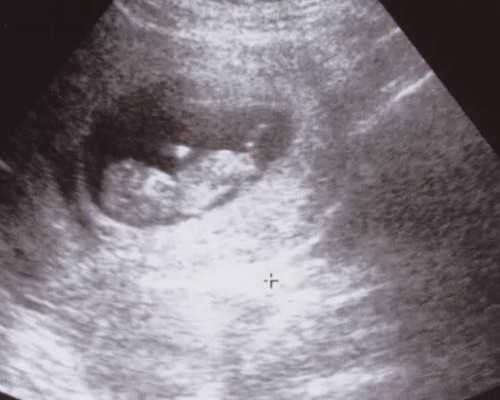

5、妊娠检测:移植手术后一段时间,患者需进行妊娠检测,以确定是否成功怀孕。如果成功怀孕,患者需继续接受产前检查和保胎治疗,直至顺利分娩。